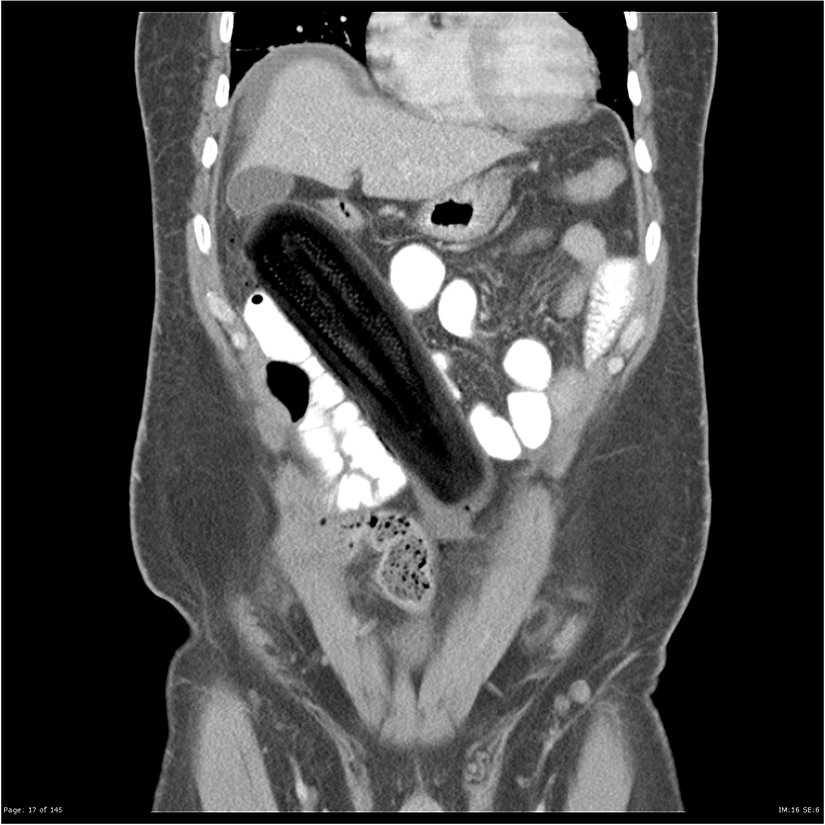

X-ray yeterince bilgi vermediği için CT çekilmesine karar verilen hastanın sorununun peritoneal boşluk içerisine sıkışmış 19 santimetrelik bir kabak olduğu anlaşılmıştır. Hastanın anal yollarla kabağı oraya sokacak kadar sert bir şekilde ittiği, anüs açıklığını yırtarak peritoneal boşluğa kadar ulaştığı öğrenilmiştir. Aşağıda CT sonucu görülebilir:

Bu tarz bir intraperitoneal kabak vakası oldukça nadirdir. Bu durum, bir insanın sert bir bitkiyi rektumu delecek kadar vücuda sokabilmesi için ne kadar kuvvetle itmesi gerektiğini düşündürmektedir.